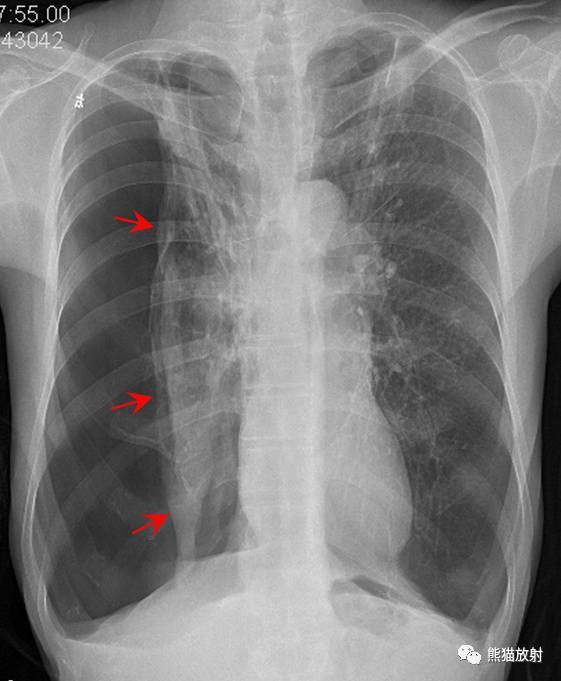

右侧气胸(肺被压缩约70%):

气带宽度略大于患侧胸廓的1/2 , 右肺明显受压 , 可见条片状高密度影 。